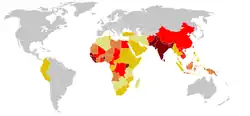

Tetanus cases reported worldwide (1990–2004). Ranging from some (in dark red), to very few (in light yellow) (grey, no data).

Tetanus cases reported worldwide (1990–2004). Ranging from some (in dark red), to very few (in light yellow) (grey, no data). -